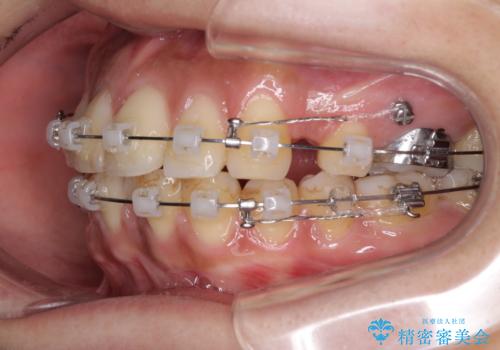

- クリアブラケット

- 2年2ヶ月

- 10-30回

上顎の前から両側の前から4番目の歯と、下あごの前歯を1本抜歯して、口元をすっきりさせる計画としました。